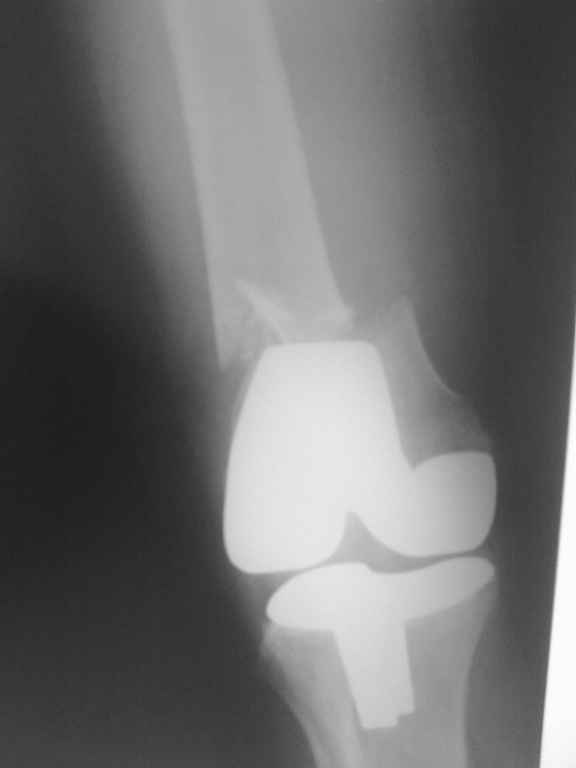

Поступила больная с перипротезным переломом

Перипротезный перелом у пациентки 67 лет . Эндопротезирование год назад . Сопутствующие нарушения ритма сердца и вес 120 кг при росте 185 .Думаю о мыщелковой пластинке с угловой стабильностью рыбинского исполнения остальное больной не потянуть . Заранее всем спасибо !

То, что планируется - наиболее распространенный подход. Еще менее инвазивный вариант - закрытый антеградный интрамедуллярный остесинтез. Мы используем гвозди, которые выпускаются предприятием ЦИТО, т.е. недорогие. Там в дистальное отверстие можно ввести 3 винта (2 снаружи и один навстречу), еще и угловая стабильность получается.